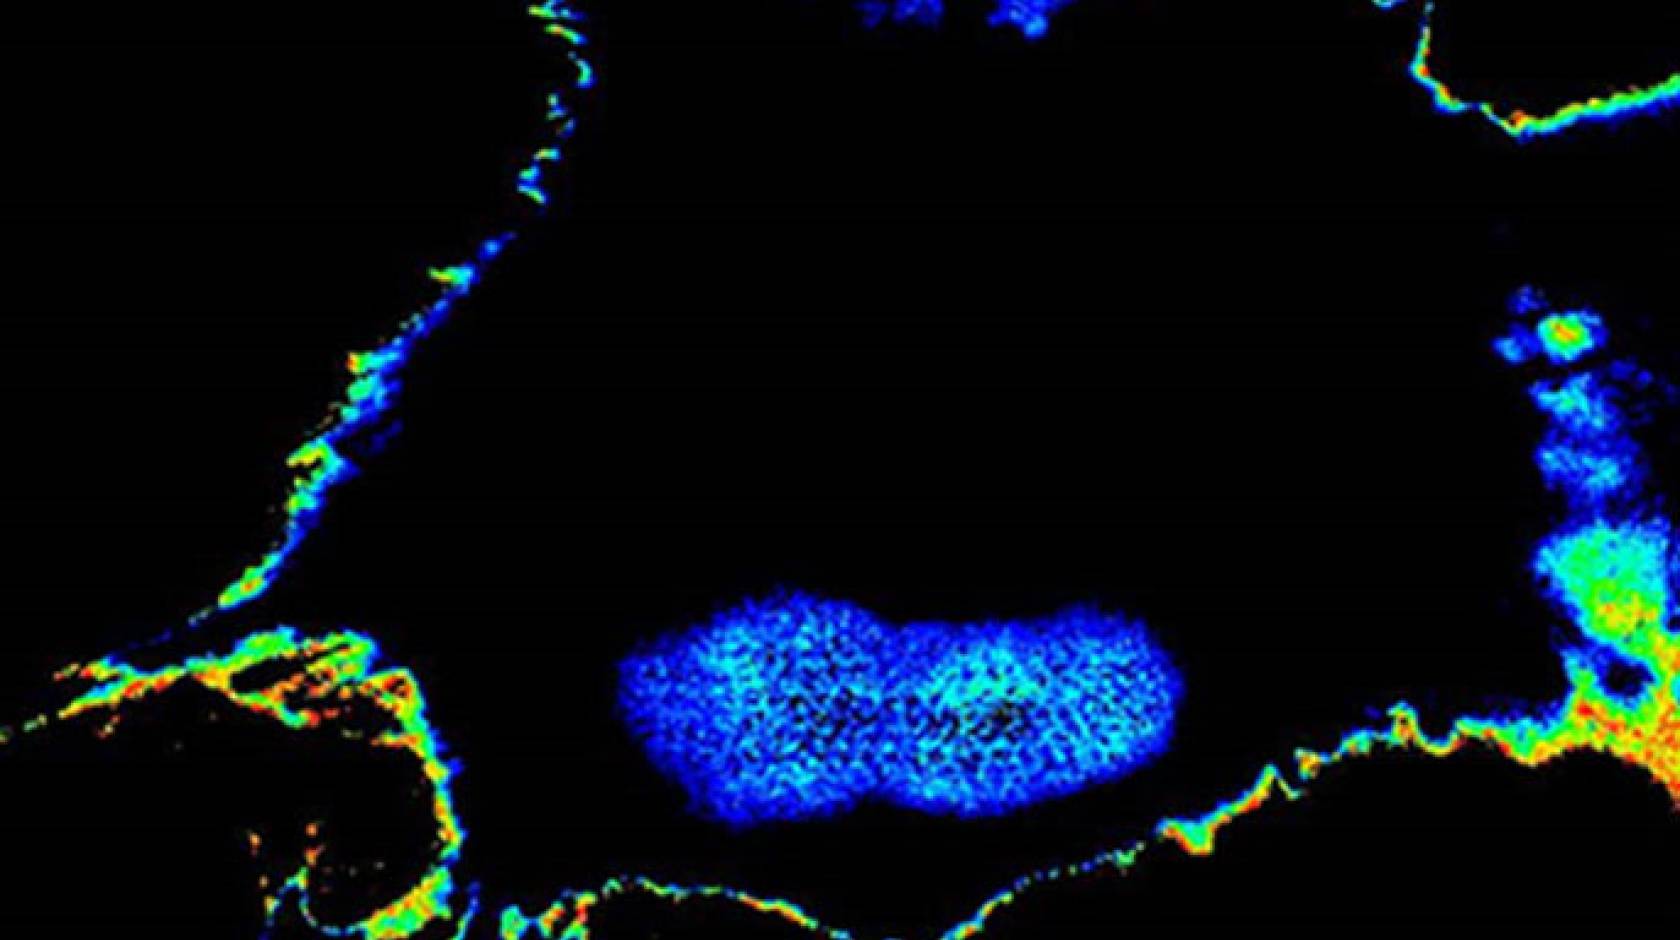

Credit: UC San Diego

The team used novel engineered biosensors and sophisticated microscopes to monitor the modification on GIV and found that, indeed, fluorescent signals reflected a tumor cell’s metastatic tendency. They were then able to measure the metastatic potential of single cancer cells and account for the unknowns of an evolving tumor biology through this activity. The result was the development of Fluorescence Resonance Energy Transfer (FRET) biosensors.